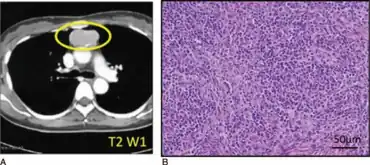

| Individual with Good syndrome a) Computed tomography findings demonstrating mediastinal abnormality b) thymus gland specimen was stained with hematoxylin/eosin | |

Thymoma with immunodeficiency (also known as "Good syndrome") is a rare disorder that occurs in adults in whom hypogammaglobulinemia, deficient cell-mediated immunity, and thymoma (usually benign) may develop almost simultaneously.[1]: 82 [2] Most reported cases are in Europe, though it occurs globally.[3]